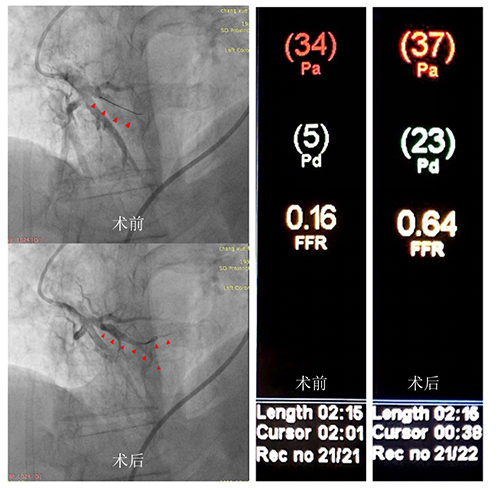

5月15日上午,在东院介入诊疗科护士长孙琳琳、技师张帅和护士廖亚军的积极配合下,血管外科主任医师张十一带领副主任医师孔祥骞、东院心外ICU主治医师张明伟成功为常先生实施了经皮腔内肺动脉成形术,同时应用压力导丝技术和动脉血流储备分数指导,既开通了血管又成功避免患者术后肺水肿的发生。

经球囊成形后,常先生肺动脉血流明显改善,并且肺静脉回流良好。动脉血流储备分数(FFR)由术前的0.16提升到0.64。压力导丝的指引使球扩效果良好,肺动脉功能已恢复,术后复查CT患者双肺无水肿。